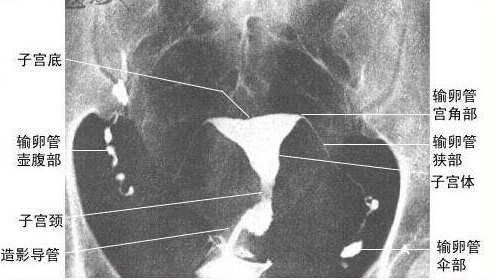

輸卵管位于子宮的兩側(cè),為一對(duì)細(xì)長(zhǎng)而彎曲的肌性管道,為卵子與精子結(jié)合場(chǎng)所及運(yùn)送受精卵的通道,內(nèi)側(cè)與子宮角相連通,開(kāi)口于子宮腔,稱為輸卵管子宮口,外端游離呈傘狀,開(kāi)口于腹膜腔,稱為輸卵管腹腔口,全長(zhǎng)8~14cm。輸卵管游離的傘部呈漏斗狀,漏斗周緣有許多指狀突起稱輸卵管傘,有[拾卵]作用。